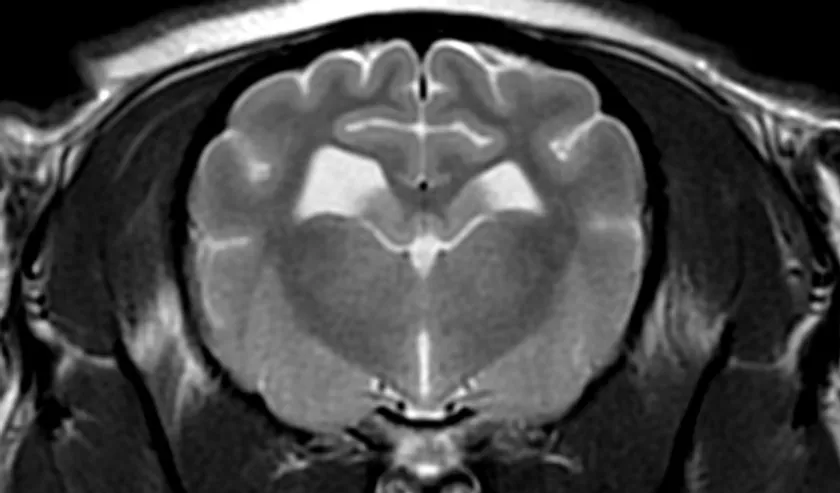

■MRI検査

強力な磁石と電波を用いて体内の水・脂肪成分の情報を収集し、断層像を得る検査です。軟部組織のコントラストが非常に優れているため、特に脳や脊髄といった中枢神経系の検査に威力を発揮します。

MRI検査画像

GE社製 1.5T MRI装置 SIGNA Explorer